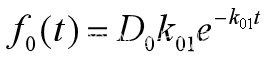

这种给药方式相当于在药物进入中心室以前,先有个将药物吸收入血液的过程,可以简化为一个吸收室,如图15所示,x0(t)是吸收室的药量,药物由吸收室进入中心室的速率为k01。

吸收室药量满足 【4.8】

【4.8】

将【4.8】代入 得到

得到 【4.9】

【4.9】

在【4.9】条件下,【3】的解为![]() 【4.10】

【4.10】

(设k01≠α,β),其中系数A,B,E由初值条件c1(0)=0,c2(0)=0确定。